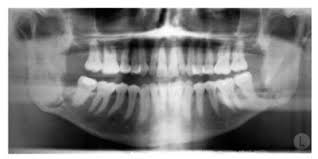

Treatment should include the alleviation ol the acute symptoms and the correction ol the underlying chronic gingival disease. If nug is left untreated it can progress to the more severe forms. Treatment is gentle debridement improved oral hygiene mouth rinses supportive care and if debridement must be delayed antibiotics. Sequela of single or multiple episodes of necrotizing ulcerative gingivitis nug signs. Characterized by necrosis of gingival tissues and loss of periodontal ligament and alveolar bone see fig.

Dental tape rather than floss. However clinical impressions suggest that periodontal attachment loss is one of the sequelae of the disease. Necrotizing ulcerative gingivitis is described as the initial stage of the condition. Diagnosis is based on clinical findings. Necrotizing ulcerative gingivitis can usually be overcome in a couple of weeks with professional dental assistance commitment to brushing flossing and rinsing regularly and minimization of risk factors.